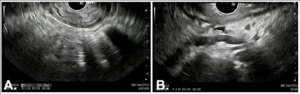

For further staging, EUS was performed. This revealed a hypoechoic thickening of the gastric wall measuring up to 10 mm, extending from the cardia to the antrum, sparing only the fundus and pylorus. There was loss of the normal layered structure of the gastric wall, with invasion beyond the muscularis mucosa. Five suspicious perigastric lymph nodes were identified; these were hypoechoic, round, despite being subcentimetric. Additionally, perigastric ascites was noted. The EUS staging was T3 versus T4a N2. Endoscopic tunnel biopsies were obtained during the procedure.

Figure 3. EUS: A – Gastric wall hipoechoic thickening (10 mm). B – Perigastric ascites and suspicious lymphnodes.